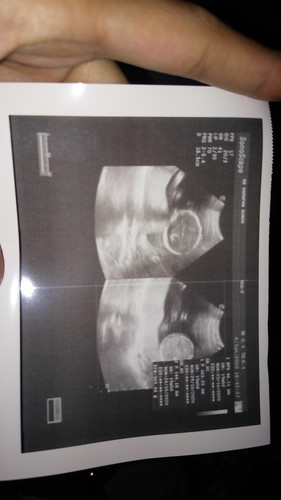

hamil 19 minggu

Normal gak ya klo berat janin udah 300 gram